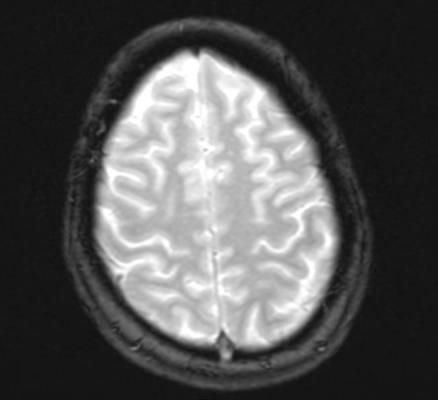

Fredrik Frejd, Ph.D., chief science officer, Affibody. “Due to the high target specificity and favorable tissue distribution properties of Affibody molecules, tumors and their boundaries can be rapidly identified and characterized, which may allow for the development of image-guided surgery as a potential option for improved brain tumor treatment.”

The study will employ commercially available state-of-the-art surgical microscopes from Leica and Zeiss that are equipped for intraoperative fluorescence imaging. Surgical signal detection and binding specificity will be the primary outcomes from the phase 0 trials. First-in-human studies with recurrent high-grade brain tumor patients will be pursued at Dartmouth. Approval for the microdosing studies will be sought under the exploratory investigational new drug (IND) pathway at the FDA.